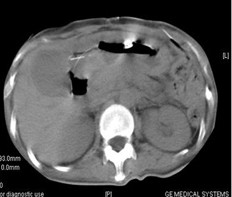

女,49岁。胃体癌晚期,胃窦增厚强化,与周围粘连,腹膜增厚,腹腔广泛转移,伴大量腹水。放/化疗失败,无法手术。治疗方案:腹腔灌注今又生2×1012VP/2次/周,共12周,同时灌注顺铂和5-氟尿嘧啶腹腔,后4周加8次全腹热疗。治疗后:第3周,腹水消失;第8周,胃窦、腹膜和网膜变薄,盆腔结节明显变小。后行手术切除残余胃肿瘤,术中探查全腹和盆腔未扪及肿瘤。术后病检胃肿瘤内未见癌细胞。

治疗前胃窦增厚强化,与周围粘紧,腹膜增厚,大量积水